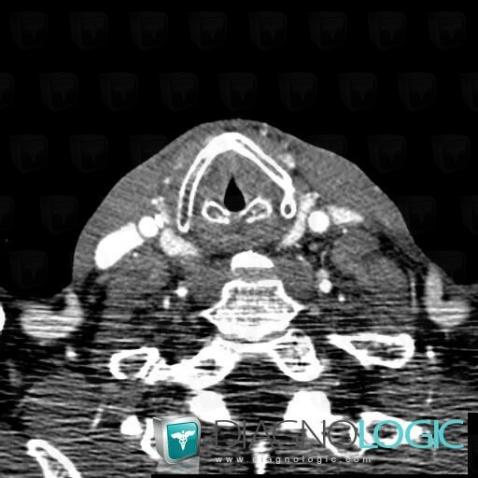

Postradiation edema, Pharyngolarynx, CT

Here is the specific information in the key image above:

- Diagnosis Postradiation edema, Location(s) Pharyngolarynx, with gamuts